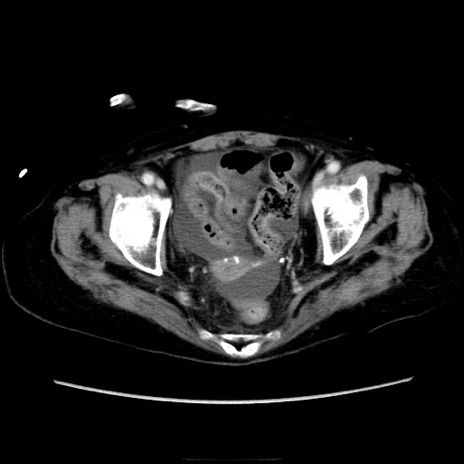

症例40(横断像)

横断像